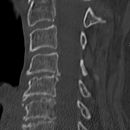

Densfraktur